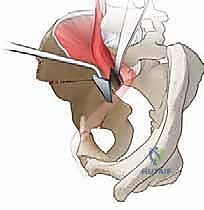

هنا تكمن عبقرية الجراحة. يقوم الدكتور هطيف بإجراء سلسلة من القطوعات العظمية الدقيقة باستخدام أزاميل ومناشير جراحية متخصصة:

1. قطع عظمة الإسك (Ischial Cut): الجزء السفلي والخلفي من الحوض.

2. قطع عظمة العانة (Pubic Cut): الجزء الأمامي من الحوض.

3. قطع عظمة الحرقفة (Iliac Cut): الجزء العلوي من الحوض.

هذه القطوعات تحرر تجويف الحُق بالكامل عن باقي الحوض، مع الإبقاء على الحلقة الحوضية الخلفية سليمة لضمان استقرار الحوض أثناء المشي بعد العملية.